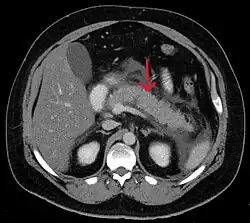

A contrast-enhanced CT scan is usually performed more than 48 hours after the onset of pain to evaluate for pancreatic necrosis and extrapancreatic fluid as well as predict the severity of the disease. CT scanning earlier can be falsely reassuring.

- Acute exudative pancreatitis on CT scan

- Calcified pancreatic duct stones with some free intra-abdominal fluid